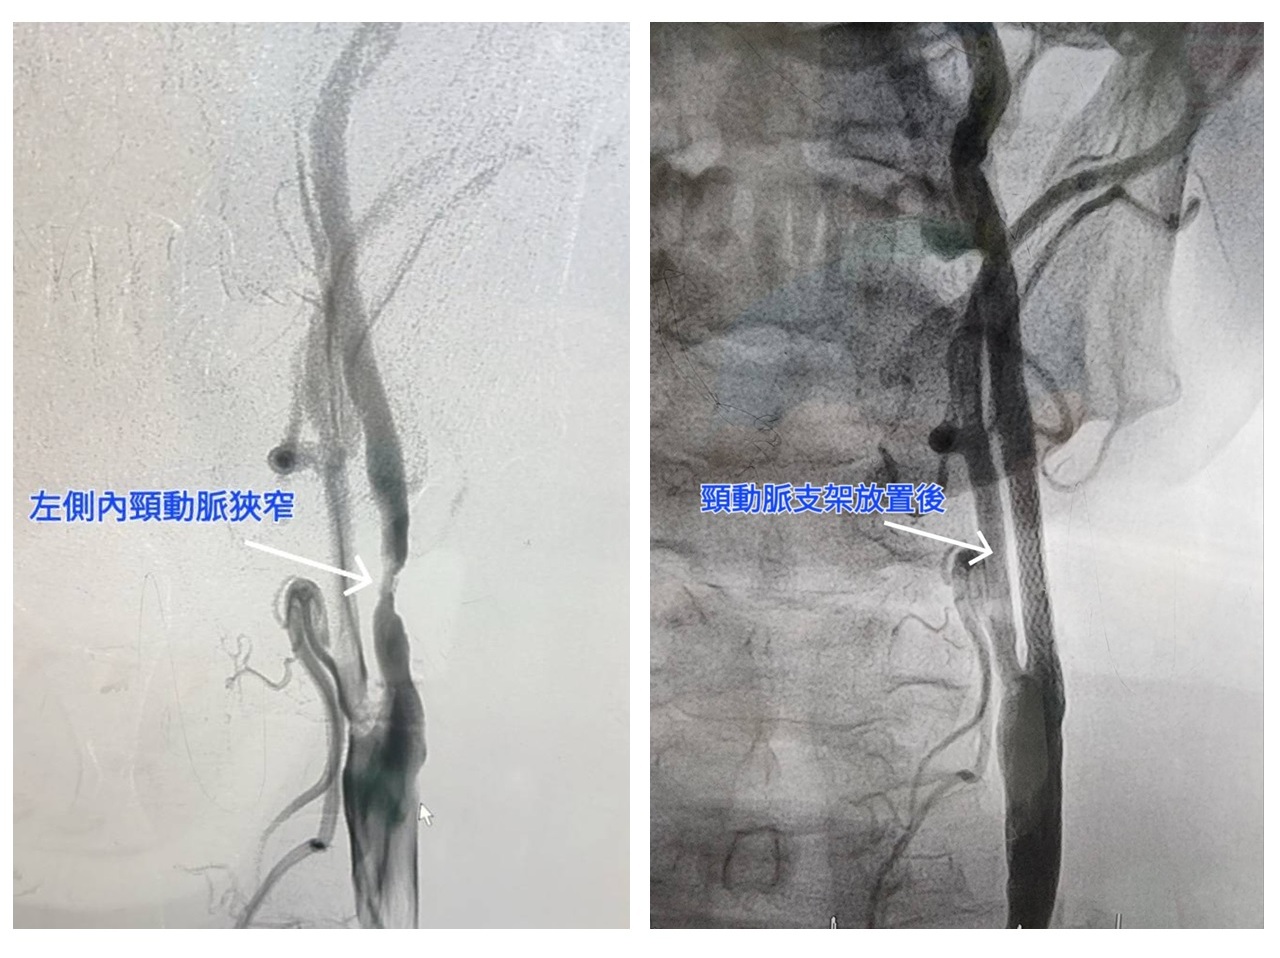

60歲的周先生有抽菸習慣,雖有高血壓卻未服用藥物控制,日前突然出現左眼視線一片黑及表達能力變差的症狀,雖然休息後會改善,但不定時又會突然發作,到醫院接受檢查,顯示為左頸動脈高度狹窄。另一位88歲的李先生,本身有高血壓病史且曾接受過心臟及左腳動脈支架置放,因連續三天出現右側手腳無力、意識不清、無法言語等情況,而到急診就醫,檢查確認為左側頸動脈高度狹窄,合併左腦灌流不全,因此出現中風症狀。兩位病人經醫師進行頸動脈支架置放術後,皆改善症狀、順利恢復出院。周先生還同步進行冠狀動脈氣球擴張術,讓中風與心臟疾病的症狀同時獲得改善。

大千綜合醫院心臟血管內科醫師羅健賢表示,頸動脈狹窄基本的治療方法為藥物治療,但當狹窄嚴重時,則須考慮頸動脈內膜切除手術或現行的微創治療-頸動脈支架置放術。頸動脈支架置放術只需局部麻醉,由鼠蹊部的股動脈穿入,經由導管到達頸動脈狹窄處後,以氣球擴張並將支架固定於狹窄處。其喉返神經受損率及治療困難度比傳統的頸動脈內膜切除手術較低,且同樣能達到預防腦中風的效果,目前的頸動脈支架置放術再加上遠端保護裝置,更可以減少併發症,施行成功率超過95%以上。